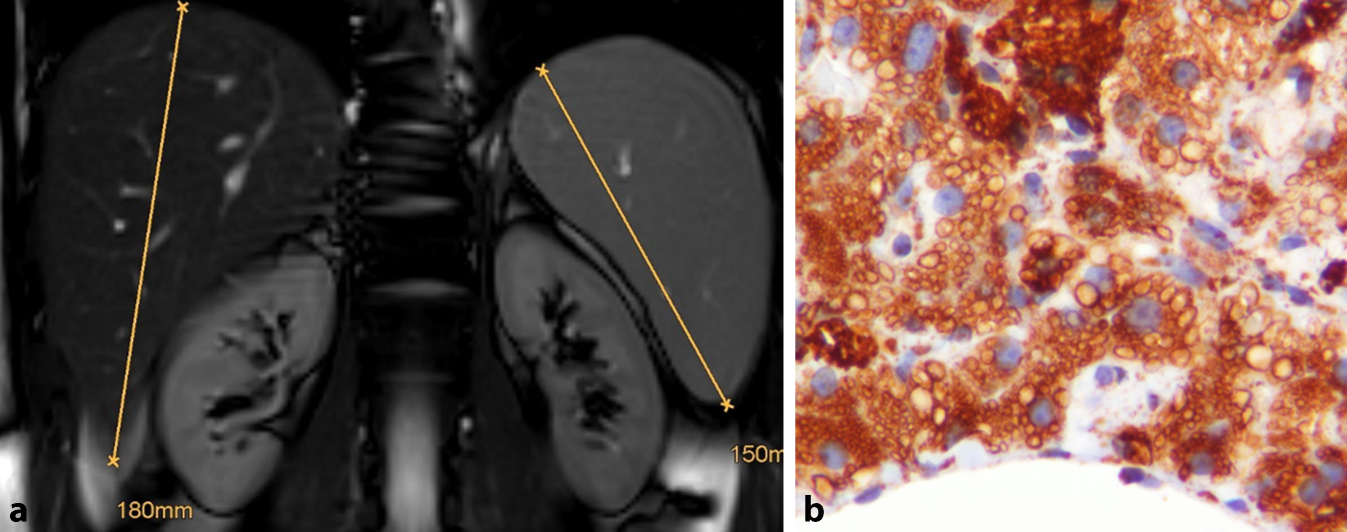

Die Folgen der Speicherung in Makrophagen stehen im Vordergrund. Es resultiert eine Splenomegalie, die im Vergleich zur Hepatomegalie dominiert. Die Milz kann nur grenzwertig vergrößert sein oder auch massiv und bis ins kleine Becken reichen. Durch die Infiltration des Knochenmarks mit Speicherzellen kommt es meist im Bereich der langen Röhrenknochen zu Beschwerden des Knochen- und Gelenkapparates mit dumpfen Knochenschmerzen, osteoporotischen Veränderungen mit pathologischen Frakturen, diaphysalen Auftreibungen (Erlenmeyer-Kolben-Deformität) bis hin zu schmerzhaften Knocheninfarkten, die typischerweise auch mit schwerem Krankheitsgefühl und Fieber einhergehen (Knochenkrise, z. B. Femurkopfnekrose; Abb. 2).

Abb. 2

Knochenmarkbeteiligung bei Morbus Gaucher bei einer 50-jährigen Patientin (a) und milde Splenomegalie (15,6 cm,) bei einem 55-jährigen Patienten (b). Dargestellt ist die typische Auftreibung der Diaphysen der Femora im Sinne der sog. Erlenmeyer-Kolben-Deformität, die analog zur Entstehung der Hepatosplenomegalie auf der Speicherung von Glukosylceramid in Makrophagen beruht